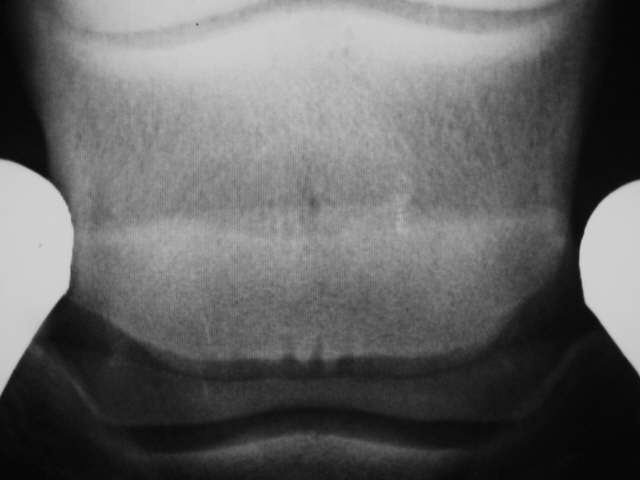

Strahlbein mit leichten Zubildungserscheinungen am oberen und unteren Rand und 3 Gefäßkanälen. Die Knochenstruktur der oberen Hälfte des Strahlbeines erscheint dichter, was verdächtig ist.